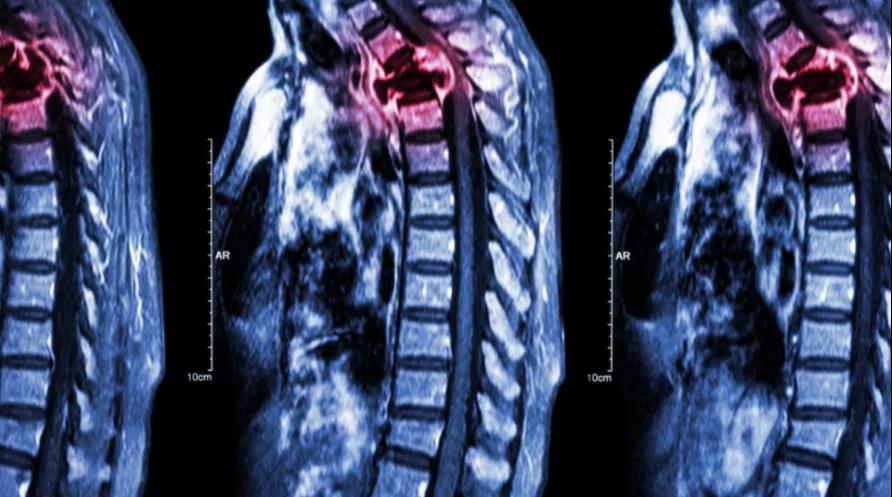

骨是肺癌轉(zhuǎn)移的好發(fā)部位,此前,國際肺癌研究協(xié)會(IASLC)的官方雜志《Journal of Thoracic Oncology》曾刊登的一篇文章中指出,約30%-40%的晚期肺癌患者會在疾病進(jìn)展過程中出現(xiàn)骨轉(zhuǎn)移,而一旦出現(xiàn)骨轉(zhuǎn)移,肺癌患者的治療將更加困難,生存期也將縮短。那么肺癌骨轉(zhuǎn)移應(yīng)該如何預(yù)防,又該如何治療了?

骨痛是骨轉(zhuǎn)移主要的臨床癥狀,病理性骨折常為肺癌骨轉(zhuǎn)移的初發(fā)癥狀,不少患者還可能出現(xiàn)高鈣血癥等癥狀,威脅生命。骨轉(zhuǎn)移的出現(xiàn)不僅對患者身體造成摧殘,還始終折磨著患者的心理。不少肺癌骨轉(zhuǎn)移患者出現(xiàn)焦慮、抑郁、死亡、孤獨等心理,終日郁郁寡歡。